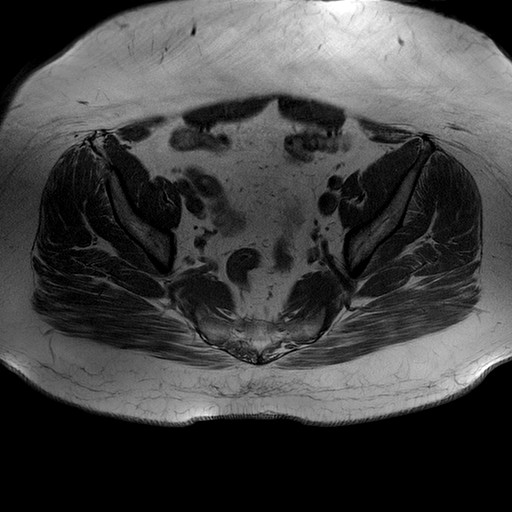

Esami: RMN BACINO

Evidenti e simmetriche alterazioni osteofitosiche in regione coxo femorale con riduzione delle rime articolari. Degenerazione completa del cercine glenoideo. Non attuali segni di versamento articolare. Non segni di edema osseo che escludono attuale algodistrofia od osteonecrosi. Lieve e simmetrica riduzione del trofismo della muscolatura glutea.